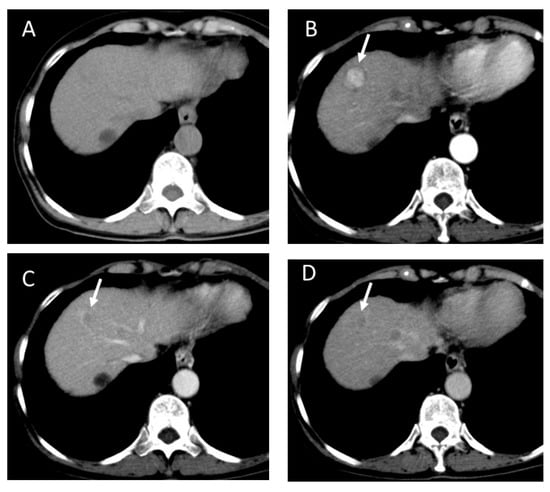

4.6. Fibrolamellar Hepatocellular Carcinoma (FL-HCC)